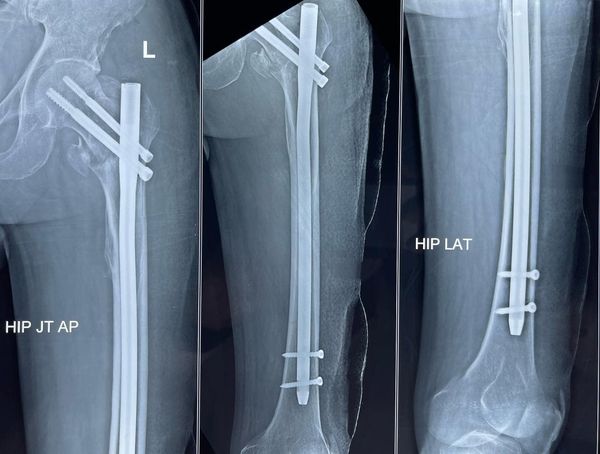

Intertrochanteric fractures of the femur that extend down into femoral shafts are sometimes tricky to handle, especially if the patient is 78 years old with multiple medical comorbidities. Such fractures should always be fixed however to give them a better chance in life, these long cephalomedullary nails (longfin) are best in such scenarios, these implants should also be used in most unstable intertrochanteric femur fractures in severe osteoporosis for a chance of better fixation.